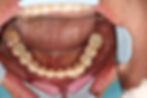

Replacing Lower mandibular teeth with 6 Neobiotech IS II Active fixtures

Treatment plan: remove 7 mandibular teeth with mobility 3, placement of 6 dental implant fixtures for fixed lower bridge.

Bridge fabricated with Neobiotech Cameleon CS 5 axis milling machine